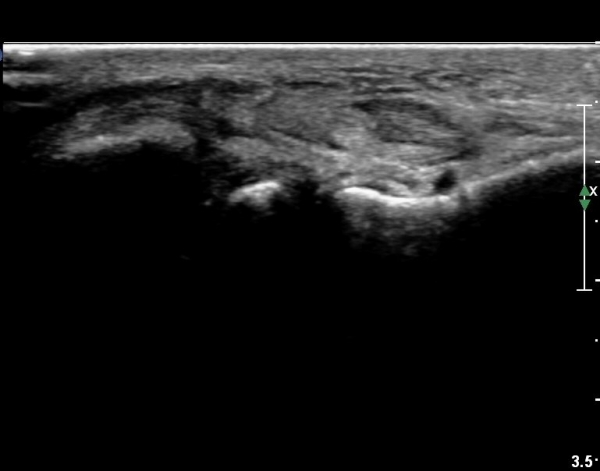

Á¾°ñºñ°ñÀδë Á¾´Ü¸é°Ë»ç¿¡¼­ ƯÀÌ ¼Ò°ßÀ» º¸ÀÌÁö ¾Ê´Â´Ù(»çÁø 6, 7).

Á¾ºñ°ñÀÎ´ë ³»¹ÝºÎÇϰ˻翡¼­ ÀδëÀÇ ¿¬°á¼ºÀº Àß À¯ÁöµÇ¾î ÀÖ´Ù(»çÁø 8). µ¿¿µ»ó  Âü°í